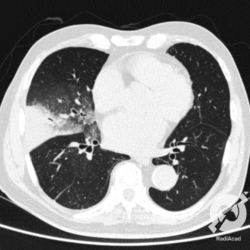

Os agentes etiológicos infecciosos são variados (bactérias, vírus, fungos, parasitas…), mas o que ocorre nos pulmões durante uma infecção por qualquer tipo de agente é a substituição do ar alveolar por secreção (pus, muco, eventualmente sangue ou necrose…) e com isso a manifestação radiográfica vai ser a mesma já que todas estas secreções apresentam a mesma densidade radiográfica: partes moles.

E o nome dado a esta alteração radiográfica que corresponde à substituição do ar alveolar por líquido é a consolidação alveolar.

Uma consolidação alveolar é, por definição, uma opacidade (imagem densa, branquinha) homogênea ou às vezes heterogênea (pela presença de calcificações ou cavidades), de limites mal definidos, exceto quando toca a pleura da parede ou das cissuras pulmonares. É um termo usado tanto em radiografia, como em tomografia computadorizada. Na tomografia, um outro termo é usado: vidro fosco, que é uma opacidade (branquinha mas não tanto como a consolidação), que borra o pulmão mas deixa ver os vasos de permeio (igual bigode de adolescente: dá pra ver todo o fundo).

Nós vamos mostrar aqui um pequeno apanhado de pneumonias de variados agentes, em diversos segmentos e lobos pulmonares, com extensões variadas. O objetivo é identificar o padrão radiológico de consolidação alveolar e não determinar o agente infeccioso, isso vai ser assunto para mais adiante. Aliás já antecipo que é fundamental saber localizar a lesão, porque alguns destes bichos gostam de determinados segmentos, alguns tumores também têm as suas preferências, então localização é fundamental. Se localização não fosse importante, um apartamento na beira do mar sairia o mesmo preço de um apartamento de frente pra BR-101, concordam?